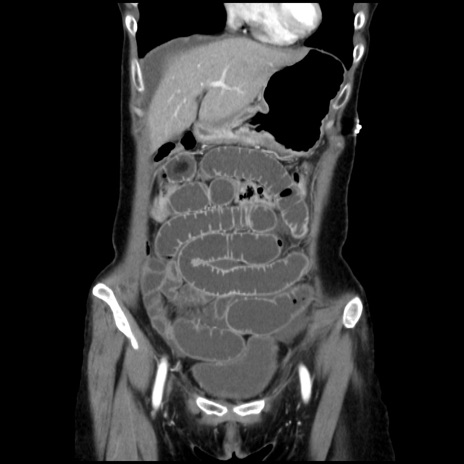

横断像

【症例】40歳代 女性

【主訴】上腹部痛、嘔気・嘔吐

【現病歴】約9時間前頃から急に上腹部痛、嘔気、嘔吐が出現。改善しないため救急要請。

【既往歴】子宮頚癌(広汎子宮全摘術、放射線療法)、腸閉塞

【身体所見】腹部:平坦、軟、腸雑音亢進、上腹部を中心に腹部全体に圧痛あり。

【データ】WBC 8400、CRP 0.03